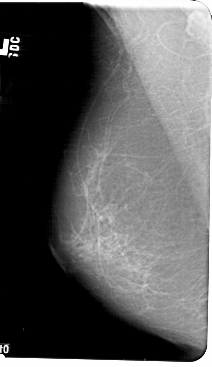

A_1405_1.RIGHT_MLO

RIGHT_MLO LINES 5491 PIXELS_PER_LINE 2941 BITS_PER_PIXEL 12 RESOLUTION 43.5 OVERLAY

FILE: A_1405_1.RIGHT_MLO.OVERLAY

TOTAL_ABNORMALITIES 1

ABNORMALITY 1

LESION_TYPE MASS SHAPE LOBULATED MARGINS ILL_DEFINED

ASSESSMENT 3

SUBTLETY 3

PATHOLOGY BENIGN

TOTAL_OUTLINES 1

BOUNDARY